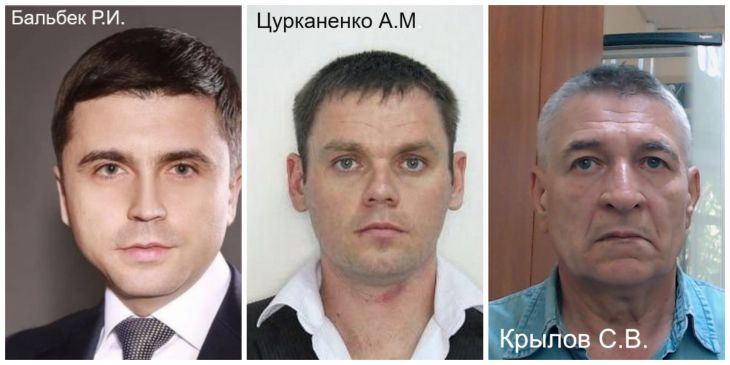

16:18, 22 марта 2023

В пятницу в Симферополе будет работать передвижной флюорограф

24 марта с 09:00 до 14:00 по адресу ул. Пушкина, д.3 жители и гости полуострова смогут пройти бесплатное флюорографическое обследование на передвижном мобильном комплексе.

Акцию проведут ГБУЗ РК «Крымский республиканский клинический центр фтизиатрии и пульмонологии», ГБУЗ РК «Центр общественного здоровья и медицинской профилактики», КРО ВОД «Волонтеры-медики» при поддержке Министерства здравоохранения Республики Крым.